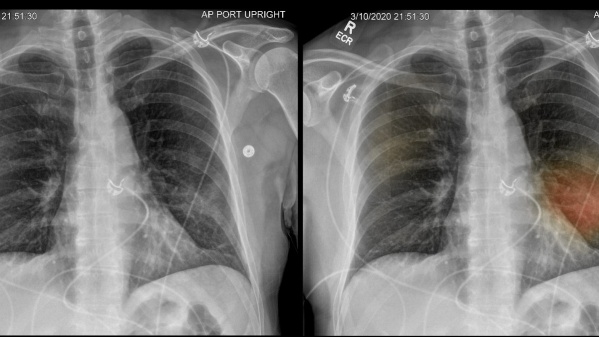

Para el estudio, el equipo de investigadores siguió a 83 pacientes con COVID-19 después de que fueran dados de alta de un hospital. El seguimiento se realizó con supervisión a los 3, 6 y 12 meses. En cada seguimiento, los participantes se sometieron a una evaluación clínica, que incluía medidas de qué tan bien estaban funcionando sus pulmones, una prueba de caminata y una tomografía computarizada de su tórax. Los resultados demostraron que durante un período de 12 meses, la mayoría de los pacientes mostraron una mejoría en los síntomas, la capacidad de ejercicio y los cambios en la TC relacionados con COVID-19. Sin embargo, algo más del 30% de los participantes todavía mostraban un funcionamiento pulmonar reducido, particularmente la eficiencia con la que sus pulmones transfirieron oxígeno a la sangre.

Además, alrededor del 25% de los participantes mostraron signos de cambios en sus pulmones en las tomografías computarizadas. “En primer lugar, nuestra investigación proporciona evidencia de que se requiere un seguimiento respiratorio de rutina de los pacientes hospitalizados con neumonía por COVID-19 -explicó Yihua Wang, coautor del estudio-. Se requiere investigar si el ejercicio programado ayuda a los sujetos a recuperarse más rápidamente. Finalmente, demostramos que la necesidad de estrategias de tratamiento para prevenir el desarrollo de cambios pulmonares relacionados con COVID-19 a largo plazo”.

Detectaron una reducción significativa en la capacidad de difusión pulmonar (DLCO) durante el período de estudio, con promedio del 77% de la predicción a los 3 meses, el 76% a los 6 meses y el 88% a los 12 meses después del alta. A un año del alta, los cambios radiológicos persistieron en e 24% de las personas. Los profesionales concluyeron que se justifica el seguimiento respiratorio de rutina de los pacientes hospitalizados con neumonía COVID-19.